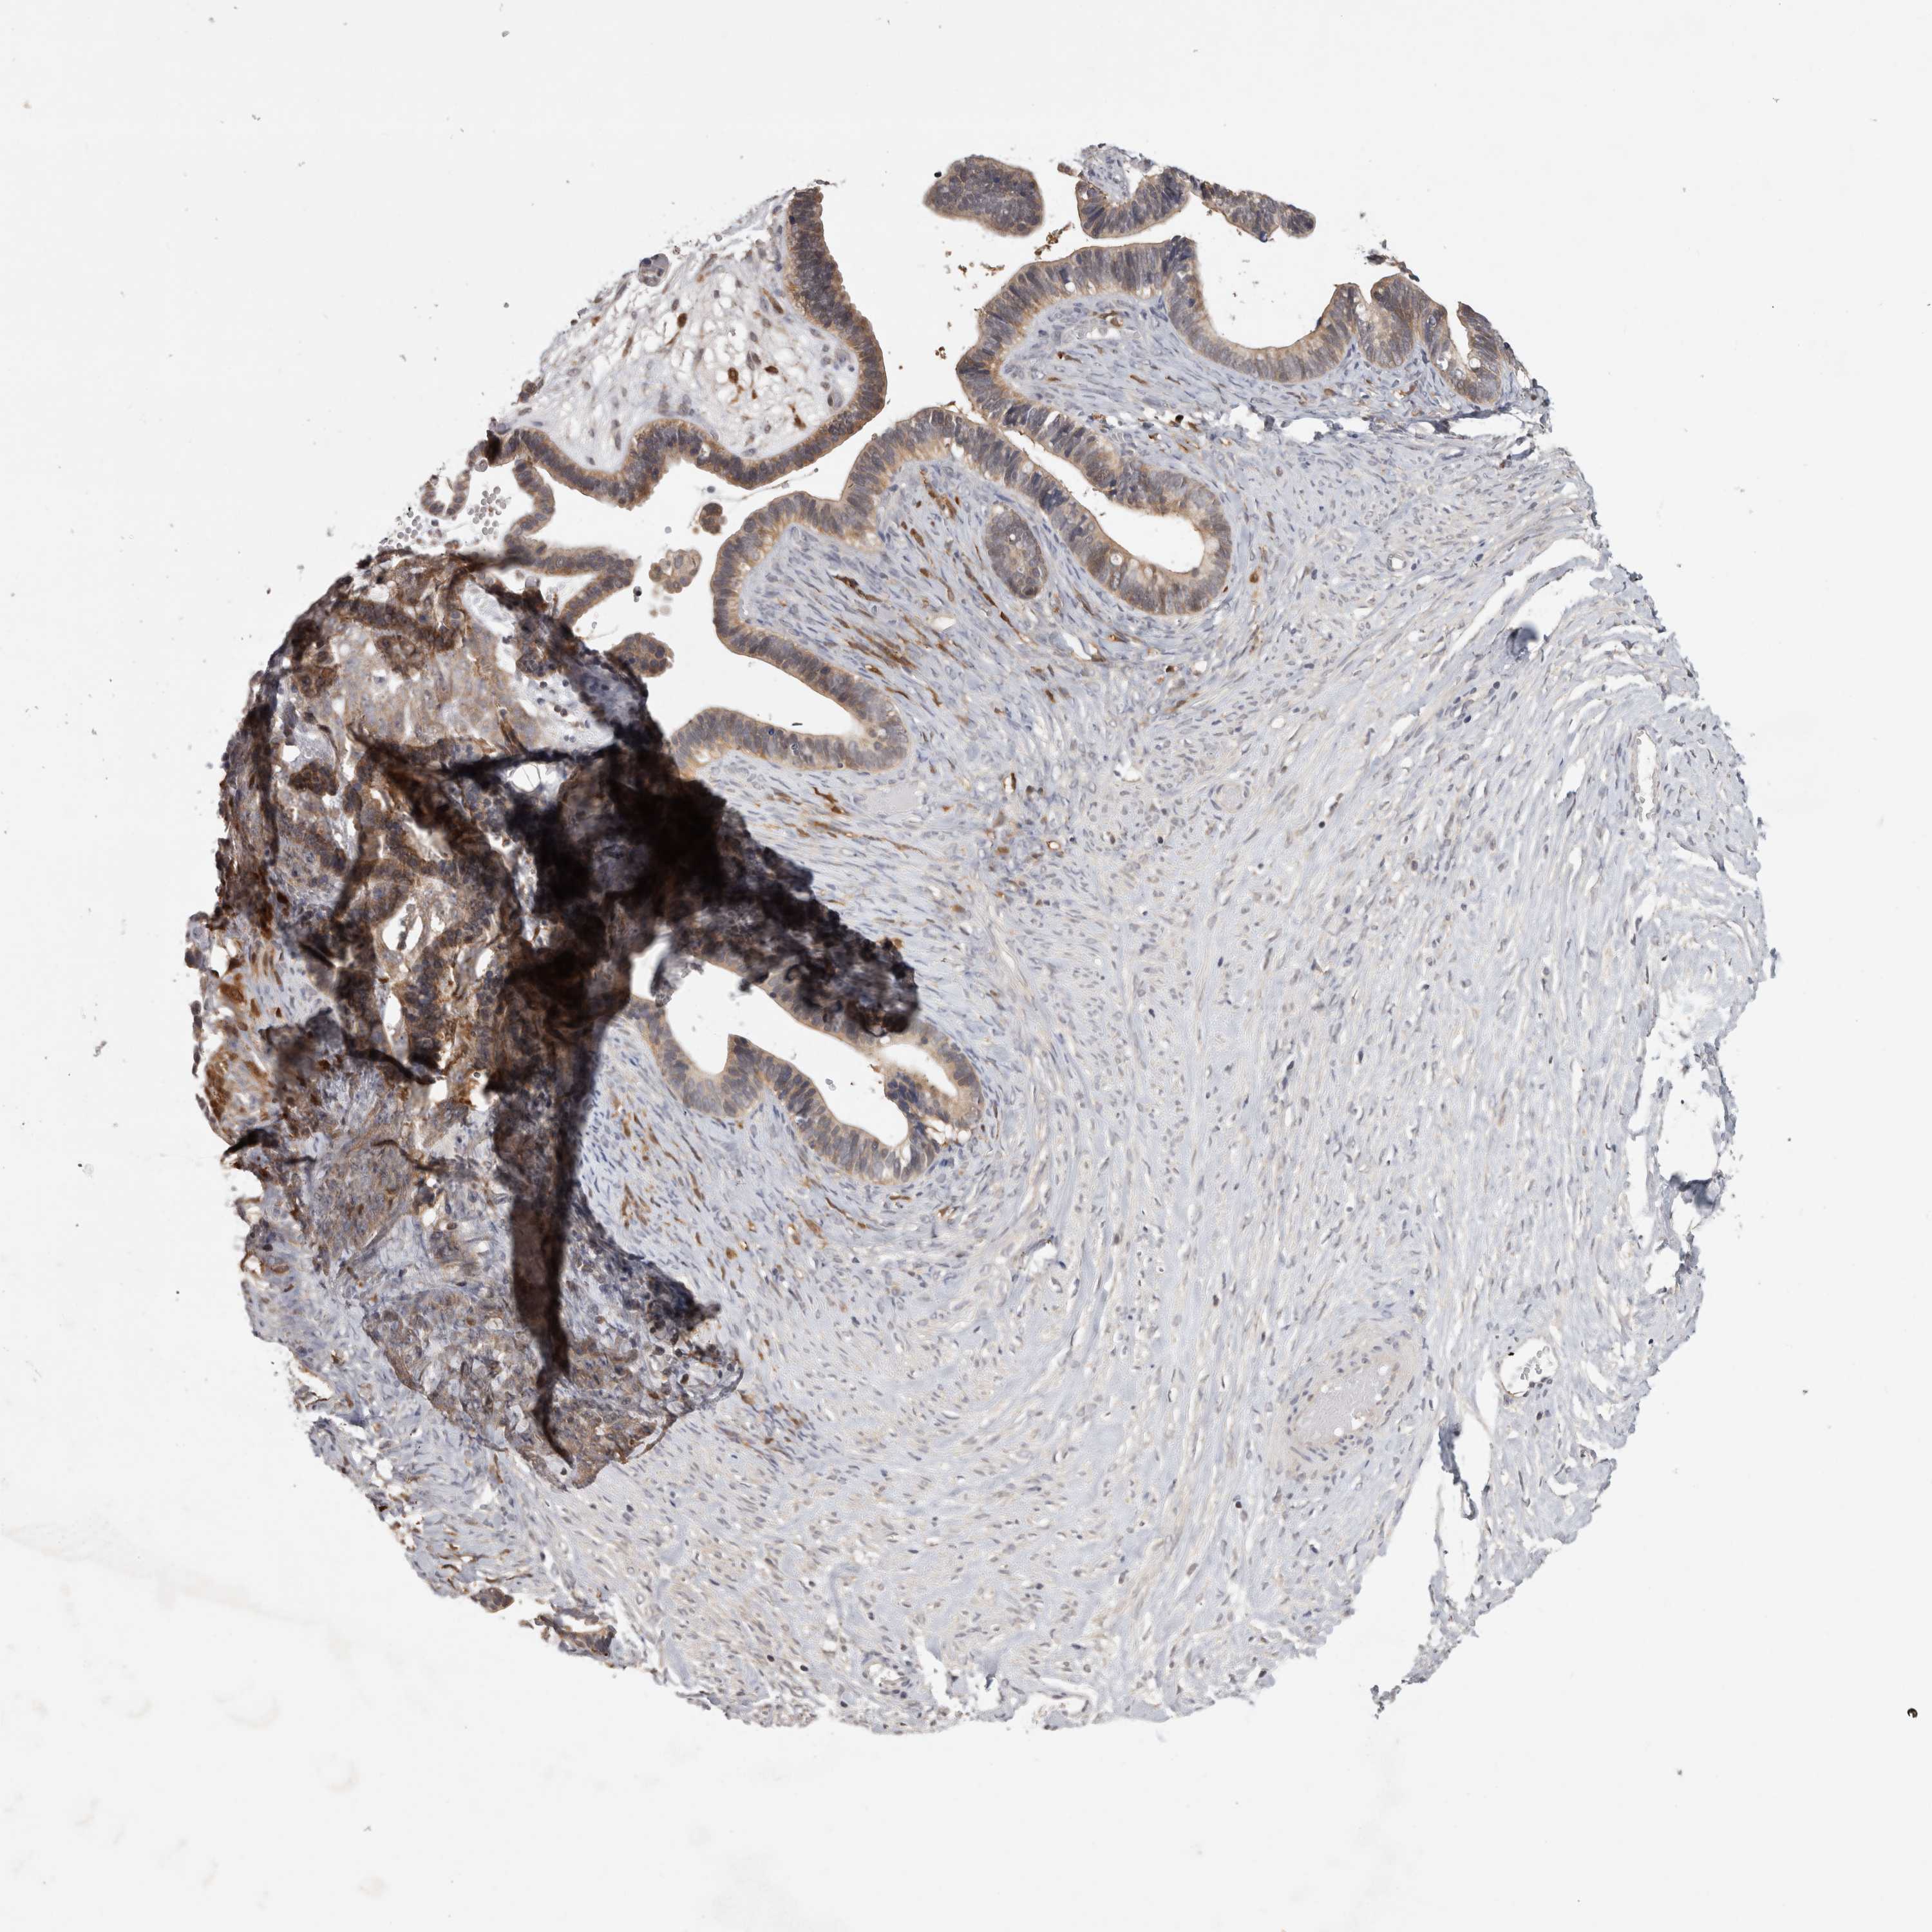

OVARIAN CANCER - Protein expressioni

A mouse-over function shows sample information and annotation data. Click on an image to view it in a full screen mode. Samples can be filtered based on level of antibody staining by selecting one or several of the following categories: high, medium, low and not detected. The assay and annotation is described here.

Note that samples used for immunohistochemistry by the Human Protein Atlas do not correspond to samples in the TCGA dataset.

Antibody stainingi

Antibody staining in the annotated cell types in the current human tissue is reported as not detected, low, medium, or high, based on conventional immunohistochemistry profiling in selected tissues. This score is based on the combination of the staining intensity and fraction of stained cells.

Each image is clickable and will lead to virtual microscopy that enables deeper exploration of all samples and also displays staining intensity scores, fraction scores and subcellular localization as well as patient and tissue information for each sample.

Antibody HPA025765

Cystadenocarcinoma, serous, NOS

Carcinoma, endometroid

Cystadenocarcinoma, mucinous, NOS

Carcinoma, NOS